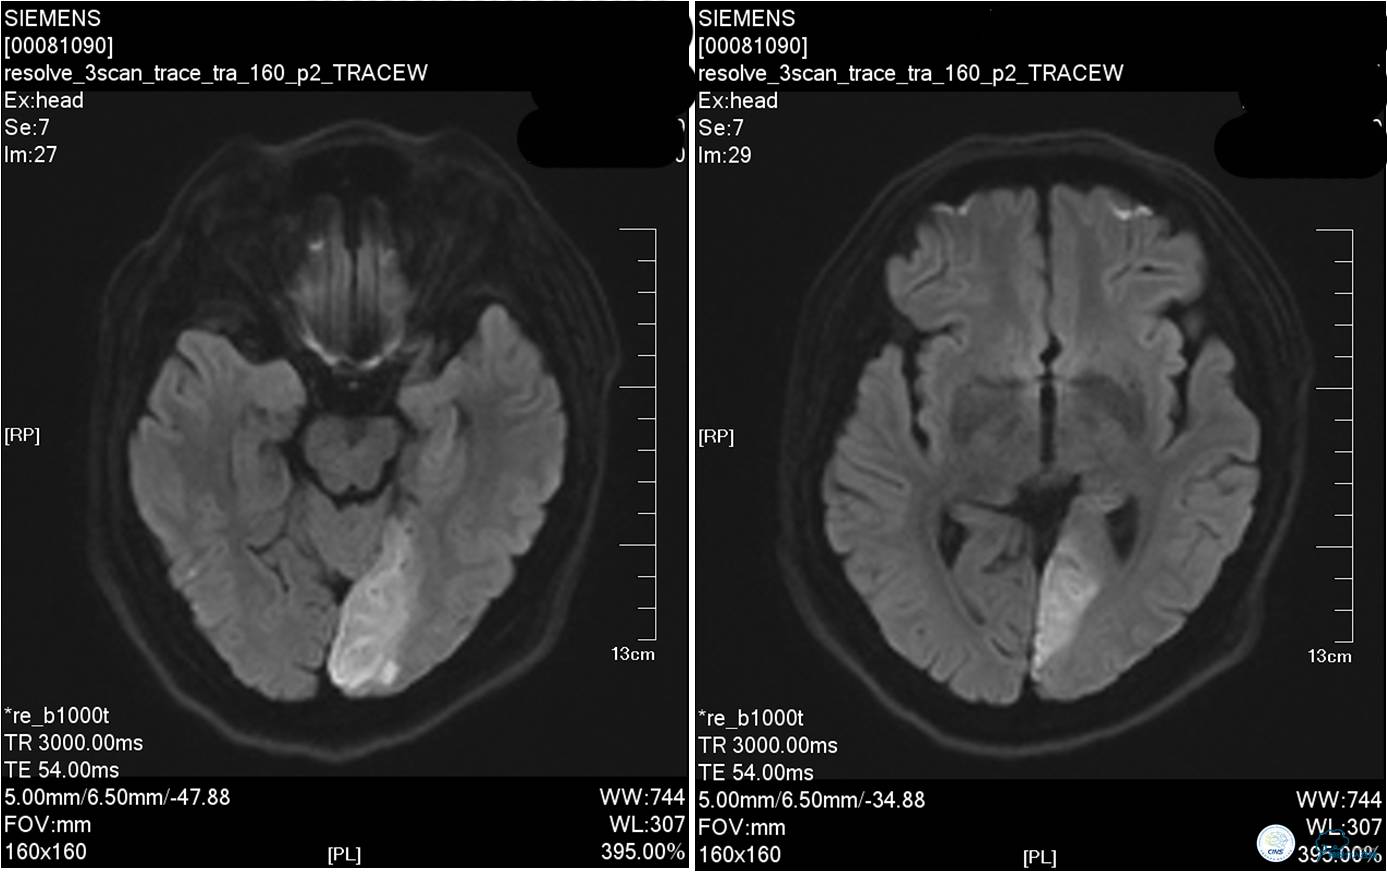

▼发病10小时后行MR检查时患者再次出现意识障碍加重。